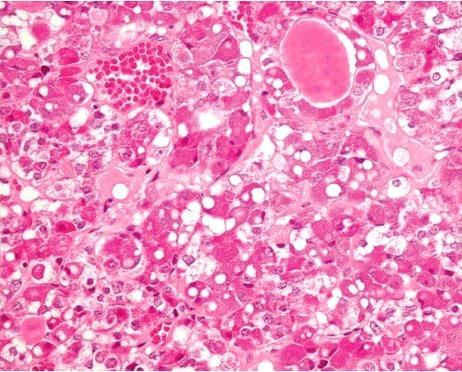

In cases of death caused by hypothermia, histological analysis can be used to determine the cause of death. Certain histological alterations of the pituitary glands in hypothermia have been reported in the literature, including haemorrhage, hyperaemia and cellular vacuolization of cells in the anterior lobe. In the present study, the validity of these morphological alterations as markers for fatal accidental hypothermia was investigated in autopsy material. A total of 34 pituitary glands in cases of verified fatal accidental hypothermia were examined histologically (haematoxylin and eosin, ferric, azan) and immunohistochemically (LCA, ACTH, C5b-9). The findings were compared with 61 cases in a control group. Hyperaemia was found in 50.0% of the study group cases and 59.0% of the control group cases. Cellular vacuolization was observed in one case (2.9%) in the study group and one case (1.6%) in the control group. Acute or recent haemorrhage in the glandular tissue was never detected. In our study, the histopathological characteristics described in the literature as pathognomonic for hypothermia could not be confirmed. Furthermore, histological differences in the pituitary glands between fatal hypothermia cases and control group cases were not observed.

在低温致死的案例中,组织学分析可用于确定死因。文献中已报道了低温状态下垂体的某些组织学改变,包括前叶出血、充血以及细胞空泡化。在本研究中,利用尸检材料对这些形态学改变作为意外低温致死标志物的有效性进行了调查。对34例经证实的意外低温致死案例的垂体进行了组织学检查(苏木精和伊红染色、铁染色、偶氮染色)和免疫组织化学检查(LCA、促肾上腺皮质激素、C5b - 9)。将结果与对照组的61例案例进行了比较。研究组50.0%的案例和对照组59.0%的案例发现有充血。研究组有1例(2.9%)观察到细胞空泡化,对照组有1例(1.6%)观察到细胞空泡化。从未在腺组织中检测到急性或近期出血。在我们的研究中,文献中描述为低温特征性的组织病理学特征无法得到证实。此外,未观察到低温致死案例与对照组案例在垂体方面的组织学差异。